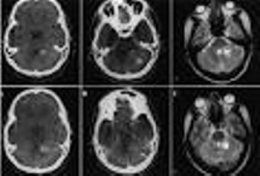

Mutismo acinético. Es un trastorno del comportamiento, caracterizado por la incapacidad para moverse o hablar en pacientes despiertos. Típicamente ha sido descrito como una complicación transitoria de la cirugía de tumores de fosa posterior.

Síndrome caracterizado por un estado silente e inerte sin actividad motora voluntaria a pesar de que se preservan las vías sensorimotoras y la vigilancia. Se asocian con esta afección la disfunción bilateral del lóbulo frontal en la que participa el giro cingulado anterior y lesiones cerebrales relacionadas. Esto puede llevar a trastornos en las capacidades de comunicación y para iniciar actividades motoras.

Este síndrome ha sido descrito en la literatura en casos de hidrocefalia con múltiples revisiones valvulares, sin relación con una malfunción valvular. En estos caso, los cambios de volumen ventricular repetitivos afectan a las vías monoaminérgicas ascendentes paraventriculares. Este mecanismo fisiopatológico explicaría la buena respuesta obtenida en algunos casos con el tratamiento con análogos monoaminérgicos, que contrasta con la ausencia de mejoría con las revisiones valvulares.

También puede aparecer como complicación de la cirugía de fosa posterior, pero con una fisiopatología que parece ser diferente. En diferentes series se ha descrito que las lesiones del núcleo dentado o de sus conexiones (las cuales no son preferentemente monoaminérgicas) podrían desencadenar la enfermedad.